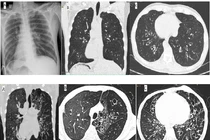

Cấp cứu vì viêm tụy cấp do sỏi mới biết toàn bộ phủ tạng đảo ngược

Đảo ngược phủ tạng là dị tật bẩm sinh hiếm gặp, di truyền theo gen lặn với tỷ lệ xuất hiện chỉ khoảng 1/5.000 đến 1/20.000 người tùy từng khu vực.